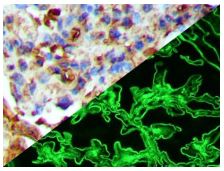

Bio SB has developed a highly sensitive Immunofluorescence and non-biotin monovalent Fab micropolymer IHC detection systems for the detection of IVD antibodies for Complement (C1q, C3c, C3d, C4c, C4d), Serum Proteins (Albumin and Fibrinogen) and Immunoglobulins (IgA, IgD, IgE, IgG, IgM, Kappa and Lambda) related to autoimmune conditions. Our innovative IF and IHC detection systems and high affinity antibodies, have opened the doors for a faster and accurate Immunofluorescence and Immunohistochemistry applicable to Autoimmune Disease like Nephropathies and Lupus.

These antibodies and detection systems are intended for use in Immunohistochemical (IHC) and Immunofluorescence (IF) applications of formalin-fixed paraffin-embedded tissues (FFPE), frozen tissue sections and cell preparations.